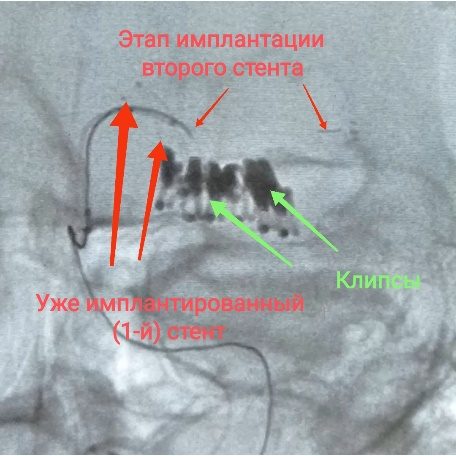

В связи с ростом аневризмы пациенту предложено этапное эндоваскулярное лечение. После предварительной предоперационной подготовки, начала приёма антиагрегантов, выполнена операция: эмболизация аневризмы бифуркации левой СМА отделяемыми микроспиралями в условиях Y-стент-ассистенции.

После установки интродуктора по обменному проводнику в левую ВСА субкраниально заведен направляющий катетер. По стандартной технике в нисходящий ствол левой СМА и купол аневризмы введены микрокатетеры Excelsior SL10. Затем из М2 в М1 сегмент левой СМА иплантирован плетеный стент LVIS Jr. Через ячейку установленного стента в восходящий ствол левой СМА введен микрокатетер SL10 и имплантирован интракраниальный стент Neuroform Atlas из М2 в М1 сегмент СМА. Затем в условиях Y-стентирования через прижатый к стенке артерии стент (техника “jailing catheter”) в аневризму имплантированы 5 микроспиралей Target. При контрольной ангиографии интракраниальные ветви левой СМА проходимы, контрастирование аневризмы отсутствует.